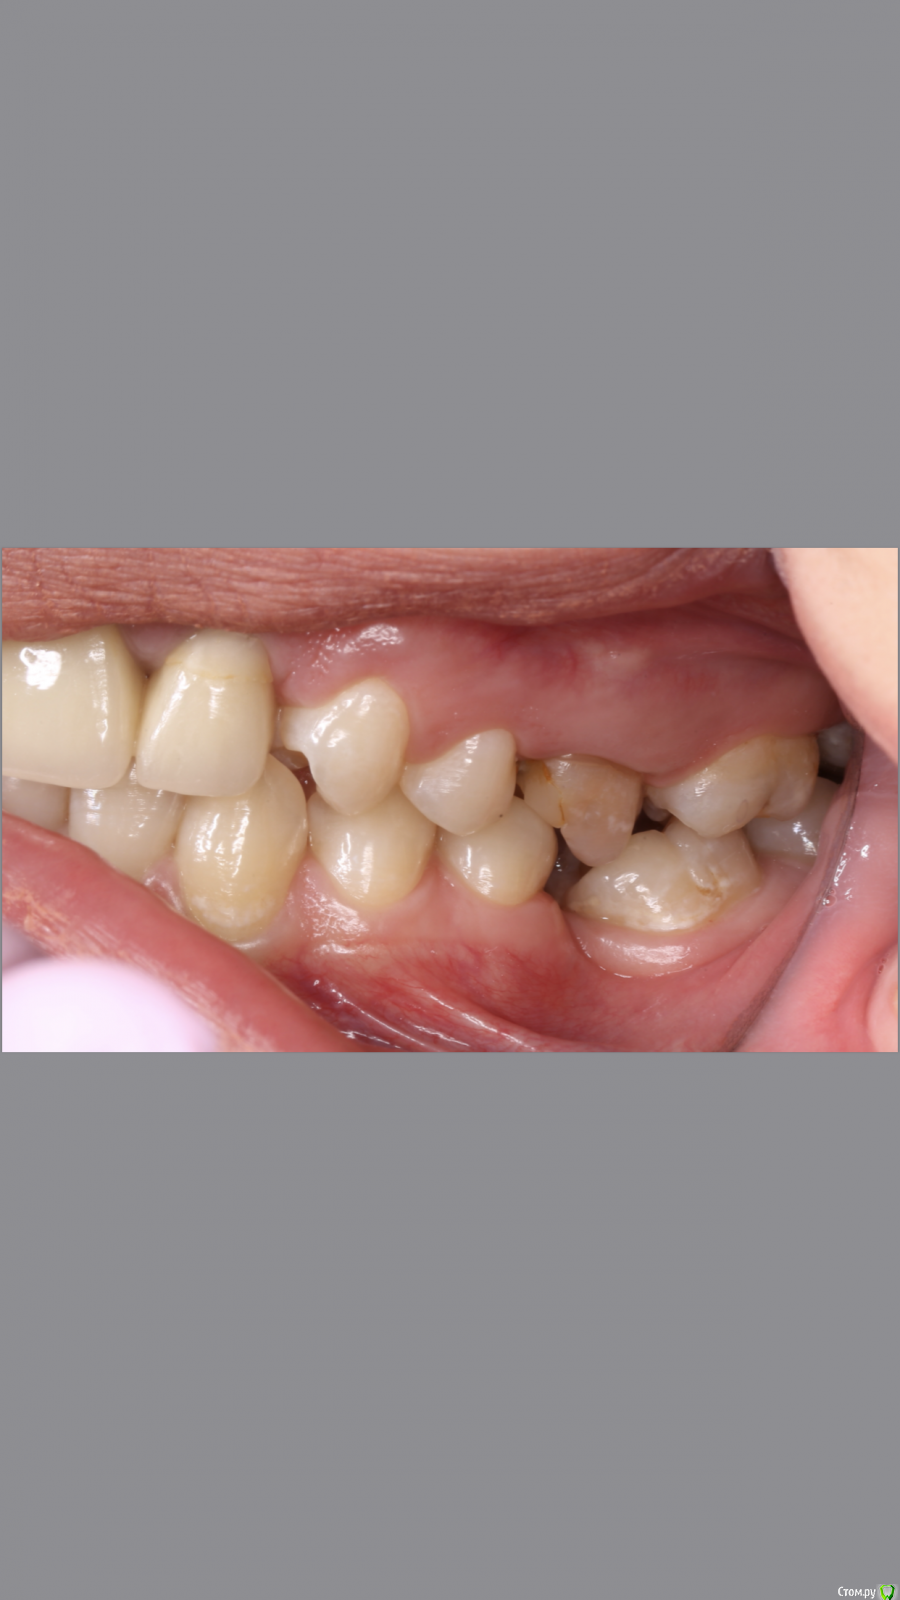

dr.Dre Опубликовано 8 июня, 2019 Поделиться Опубликовано 8 июня, 2019 Добрый вечер.Коллеги помогите грамотно скласть план лечения?С чего начинать ,терапия,ортодонтия ортопедия Ссылка на комментарий

Monkey Опубликовано 19 июня, 2019 Поделиться Опубликовано 19 июня, 2019 Добрый вечер.Коллеги помогите грамотно скласть план лечения?С чего начинать ,терапия,ортодонтия ортопедияСанация, удаление 8-х, ортодонтическое лечение с раскрытием места 36,23 (заодно и среднюю линию откорректируете), протезирование Ссылка на комментарий